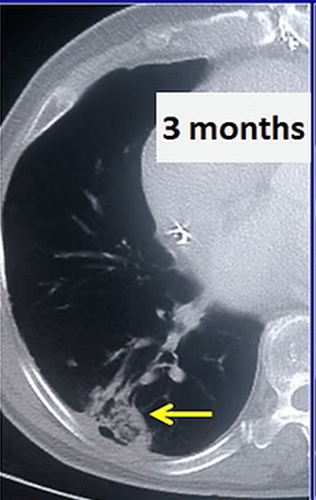

In our patient who had a 4x2cm non small cell lung cancer, cryoablation was performed. After the procedure, the 3 and 6 months control CT images show progressive shrinkage of the tumor.